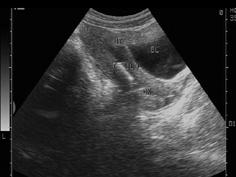

女性,27岁,上环3月,月经量多,超声检查见图,最可能的诊断是 ( )A、节育器下移B、节育器嵌顿C、盆腔炎D、子宫内膜炎E、宫颈炎

问题 女性,27岁,上环3月,月经量多,超声检查见图,最可能的诊断是 ( )

选项 A、节育器下移 B、节育器嵌顿 C、盆腔炎 D、子宫内膜炎 E、宫颈炎

答案 A